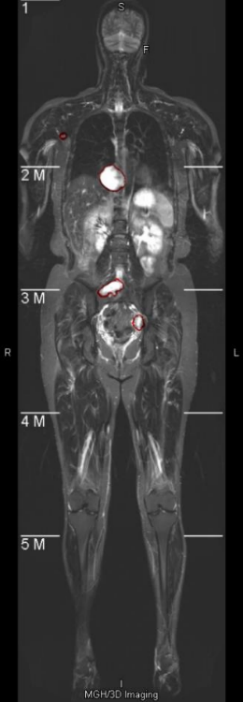

The experimental hardware environment mainly consists of GPU cards that support deep learning, with the model being NVIDIA Tesla V100, quantity 1. As for the software environment, Ubuntu 16.04 operating system, VSCode development environment, Python as the development language, and TensorFlow, Keras, and PyTorch development platforms are used for single-model deep learning training. The WBMRI image data of neurofibromatosis patients in the experiment comes from a collaboration between Harvard Medical School and tertiary hospitals in China. The dataset includes 158 cases with a total of 1380 tumors, and five-fold cross-validation is performed. The segmentation annotations are completed by domain experts, and the target detection annotations are automatically generated using the minimum rectangular box of the segmentation area.

Each WBMRI sequence includes about 20 DICOM format scan images. For target detection training, the image sequence is first converted to 8-bit grayscale images with the original resolution of 322×1086. Since the width and height of the original images vary, it has been empirically proven in academia and industry that deep learning performs better on square two-dimensional images. Therefore, the images need to be adjusted to squares. The image background is black, and the smaller side of the image is directly padded with the background color value to expand the boundary. After the boundary is expanded, the scanned object does not deform and remains centered in the image. At this point, the resolution is 1086×1086. Then, each scanned image is resized to 512×512, and in three-dimensional space, all are resampled to 512×512×32. After resampling, the single-layer two-dimensional images are enhanced according to the algorithm described in Section 2.2 of this paper, and then the images are normalized. The pixel values of all images are divided by 255 to convert them to a numerical range of 0-1. For 2D target detection, the input image size is 512×512, and random image augmentation is performed during training. The random combinations of augmentation methods include horizontal flipping, vertical flipping, random rotation within 90 degrees, and random scaling and translation within a range of 10%. For 3D segmentation, the input patch size is 32×32×32, and no data augmentation is performed during training.

Neurofibromas may be distributed to any part of the body, mainly including the legs, arms, head and neck, chest, abdomen, and pelvis. The volume can also vary from a few cc/ml to several hundred. In the following display, 7 representative images will be selected, covering different parts of the body and volumes ranging from 5cc/ml to 500cc/ml. As shown in Figure 4, it is a comparison between the integrated learning method proposed in this paper and the detection results of 8 single-models. Here, GT, ED, YL, CR, CC, DINO, and GAN respectively represent Ground-Truth, EfficientDet-D7, YOLOv7, Cascade R-CNN, 3DConvCaps, Mask-DINO, and TransGAN. All detection results are predicted after being processed by the image enhancement algorithm proposed in this paper. From the display results, it can be seen that the detection results of the integrated learning method in this paper are basically consistent with the Ground-Truth, with only a small amount of difference near the boundary.